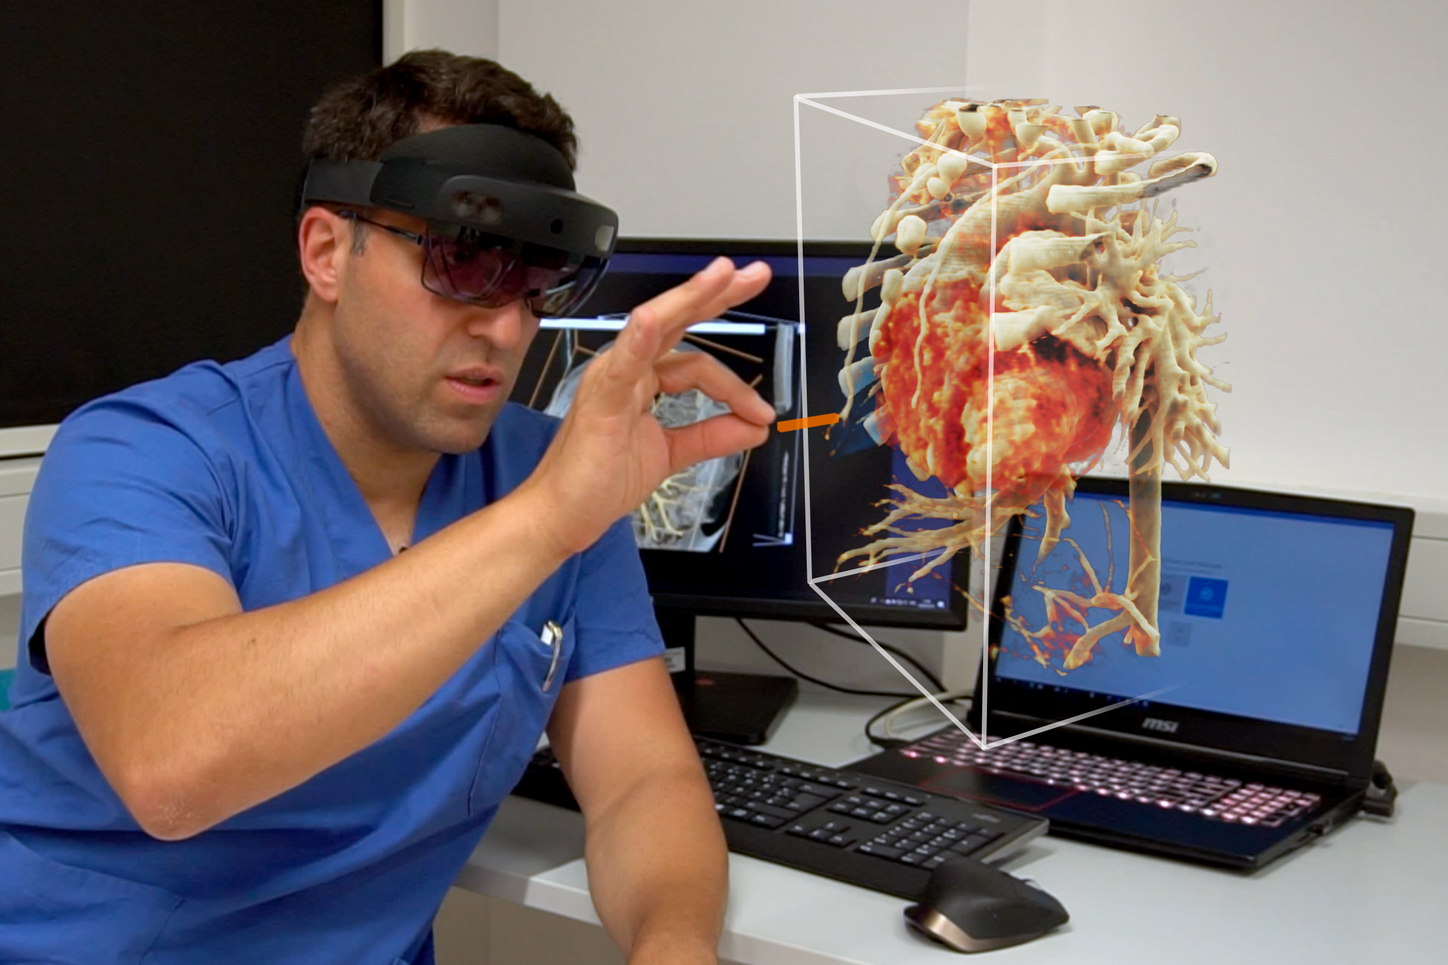

Visualize the smallest structures of the heart realistically without surgery? About the use of a prototype that makes this vision almost tangible.

Cardiac surgery is one of the most difficult procedures, and it gets even more complex when it comes to operating on tiny children’s hearts. Visualization techniques like cinematic rendering provide a detailed 3-D view of the patient’s heart and surrounding anatomy. But what happens when these images are turned into a hologram that can be rotated, zoomed, and looked at from all possible perspectives?

The combination of cVRT and HoloLens 2 is still in a prototype state and not commercially available yet.